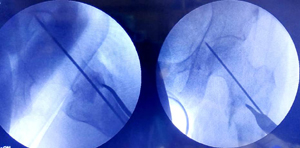

Case 2

A 32-year old male with a road side accident, presented with intertrochanteric fracture of the right femur (AO/OTA 31-A2). The patient was submitted to osteosynthesis with PFN. Immediate post-operative radiograph of the patient revealed acceptable NSA, acceptable position and size of screws, restoration of medial buttress. However anterior bony contact was lacking (lack of anterior buttress). Patient was on regular follow-ups, and at 5 months post-operative he developed varus collapse and reverse Z-effect. Gradually superior derotation screw migrated laterally, with inferior lag screw migrating medially. The resultant varus collapse headed to perforation of the femoral head by the inferior lag screw (reverse Z-effect). As fracture was uniting, we removed the inferior lag screw and tightened superior derotation screw, which lead to successful union of fracture at 9 months. Radiographic images of the patient are presented in Figure 7.

Figure 7b Immediate post-operative radiograph showing restoration of NSA & medial buttress. Also note the acceptable position & size of screws. Arrow in lateral view showing lack of anterior bony contact.

Figure 7c Three months post-operative radiograph showing development of varus at fracture (arrow) and backing out of hip screws.

Figure 7d Five months post-operative radiograph showing varus collapse (long arrow) and differential migration of the hip screws (small arrow), with the caudal one migrating medially & perforating the head (typical of the reverse Z-effect).